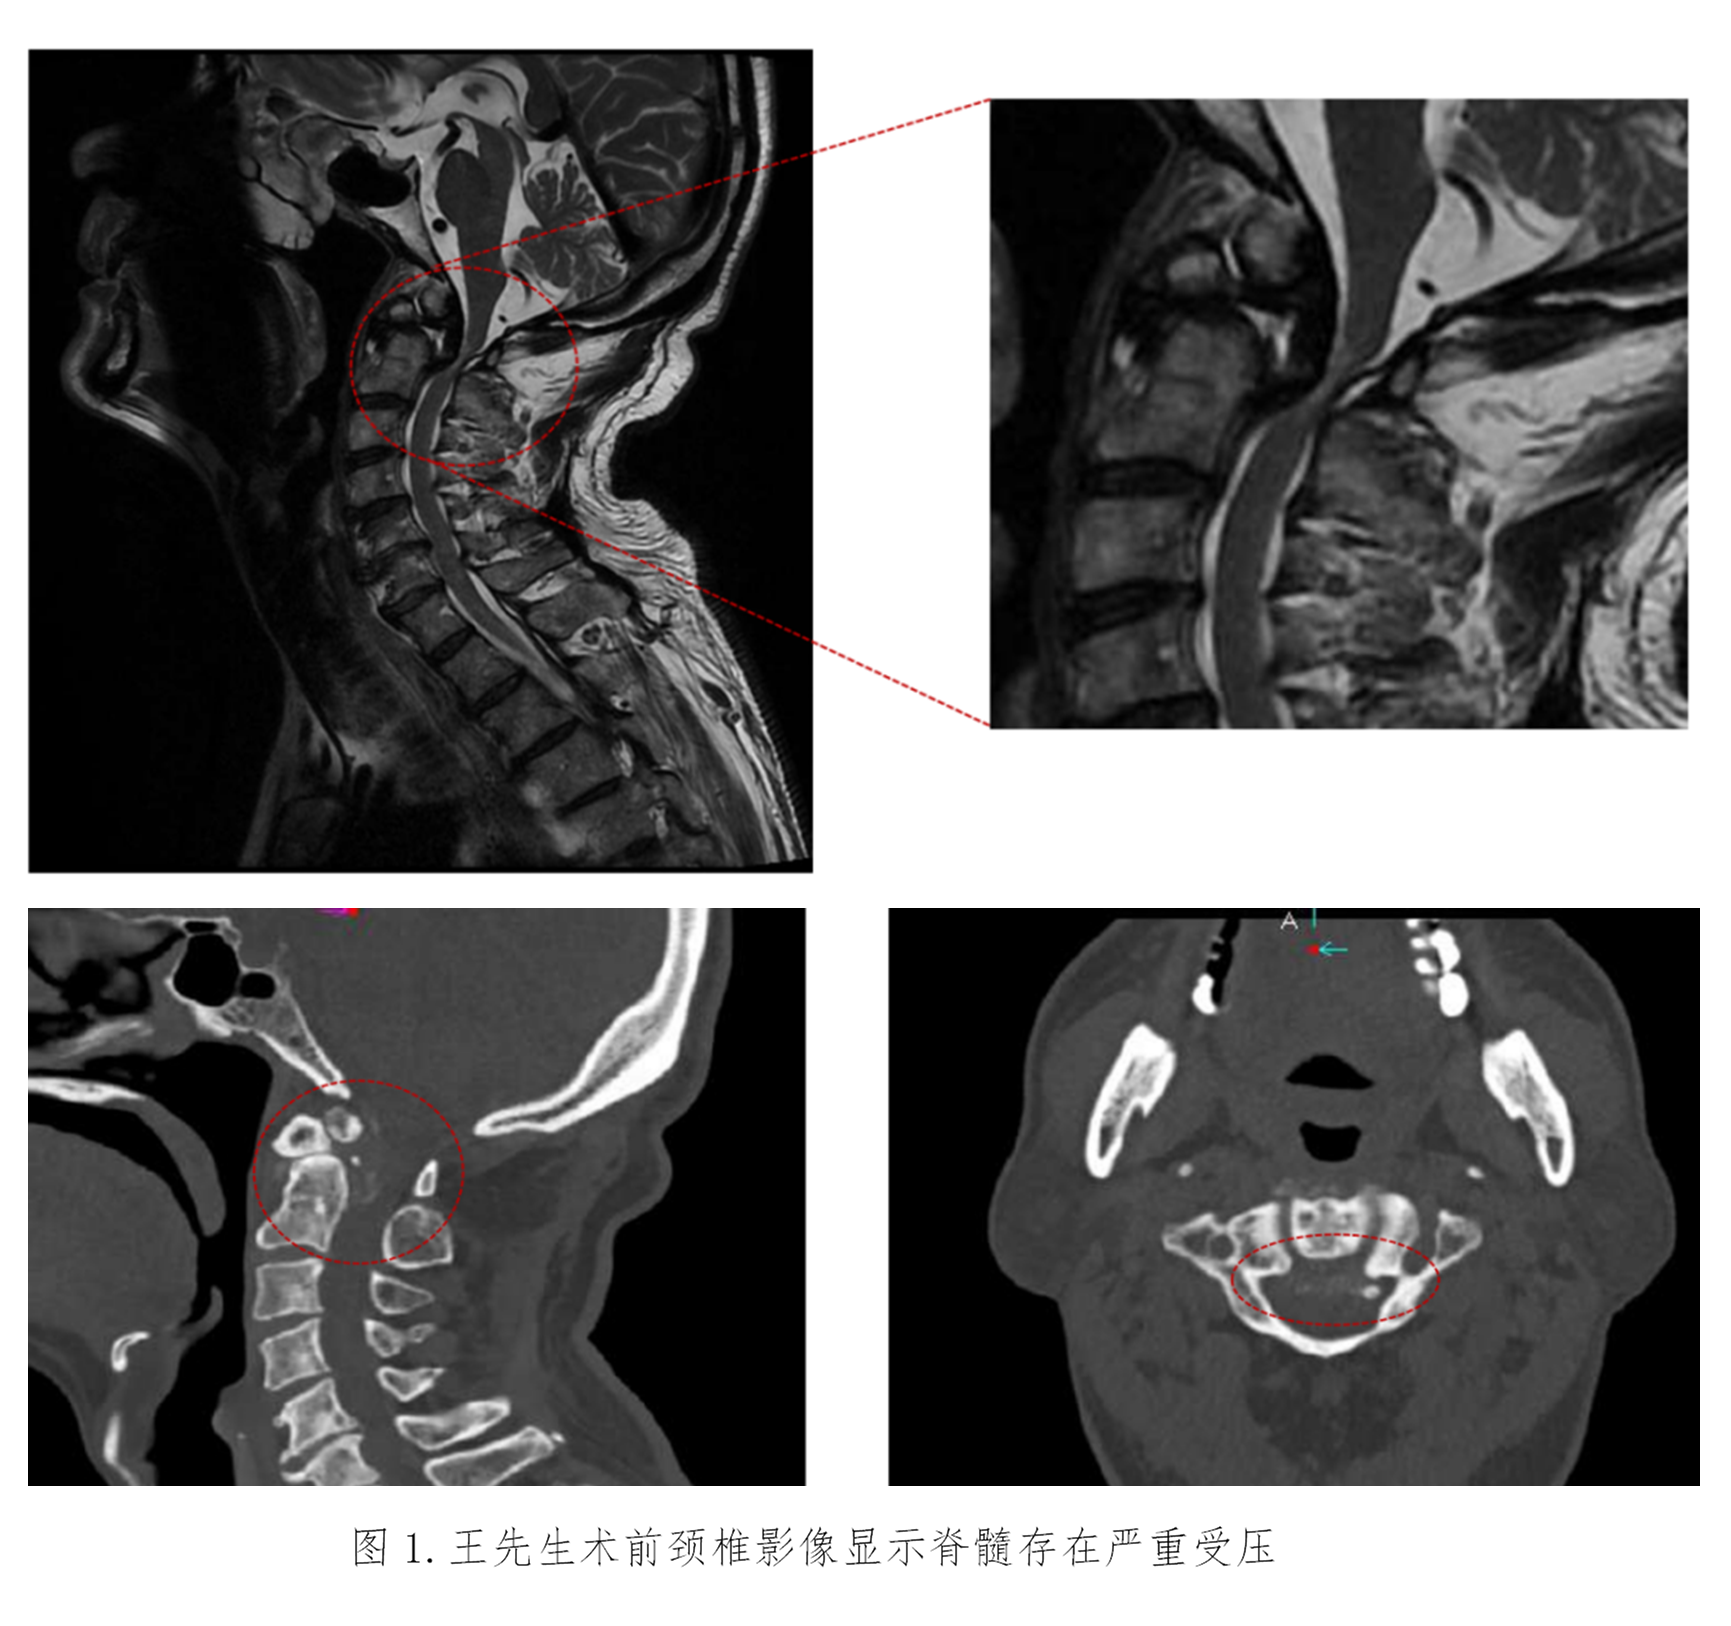

患者王先生已72岁,四肢乏力进行性加重10年,伴左下肢跛行4年,因担心需要手术治疗而没有正规就医。近期已无法独立行走,经推荐来到苏大附四院姜为民主任门诊就医。王先生的查体结果表现出明显的高位脊髓损伤症状:左上肢肌力下降至4级,左侧霍夫曼征、踝阵挛及巴彬斯基征均为阳性,左足下垂;右侧病情稍轻。影像学检查显示“游离齿状突畸形”——即第二颈椎(C2)齿状突发育异常并游离,后缘异常增生导致上段颈髓严重受压,脊髓功能受损使得患者近年来行走能力不断下降,并因此频繁跌倒,这对患者的生命安全构成了极大威胁。

颈椎手术尤其是上颈椎手术的难度与风险很高,常被誉为刀尖上的舞蹈。术前的全面检查显示,该例患者与常见的上颈椎游离齿突畸形不同——引起颈髓损伤的主要原因不是寰枢椎不稳,而是齿突后方的异常骨性增生严重压迫脊髓所致。目前常用的手术解除脊髓压迫方法是经口咽途径直接切除游离的齿突及增生的骨性结构,再从后方行枕颈固定融合。但是这种手术不仅难度高而且有大量并发症风险,更是会令患者失去头部旋转功能的风险。最初姜主任团队一度考虑采用该常规手术方案,但对于这位72岁的高龄患者而言,创伤与风险是巨大的。

图3:术后复查CT见骨性减压充分